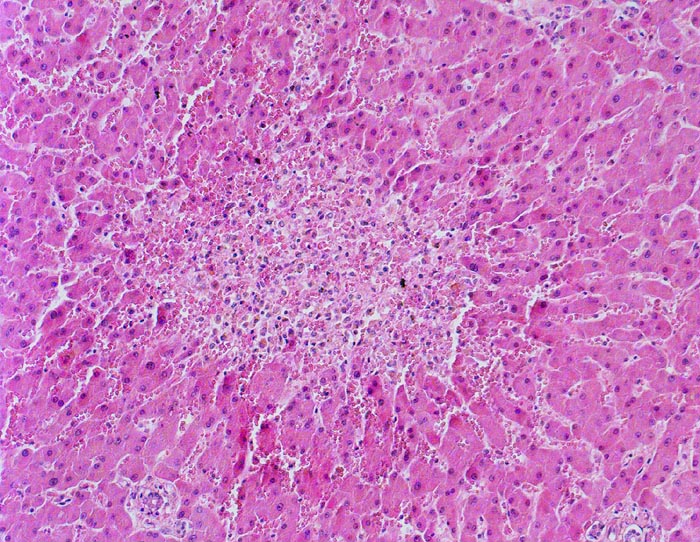

Zonale perizentrale Parenchymnekrose bei Schock

Im Bildzentrum die Zone 3. Ein Zentralvenenlumen ist nicht erkennbar. Anstelle von regelrecht aufgebautem Parenchym ist eine blutdurchtränkte Zone mit Entzündungszellen anstelle von Hepatozyten getreten. Die Sinusoide der Zone 2 zeigen eine Blutstase.

Schweres akutes Rechtsherzversagen bei multiplen zentralen und perizentralen Lungenembolien.